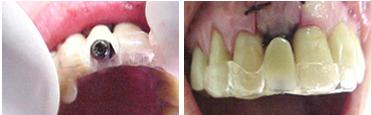

Figura n°15. Prova estética do pilar.

Figuras n°15, A e B. A) Preparo do pilar utilizando a broca diamantada em alta rotação. B) Vista do pilar em posição no modelo de trabalho, sobre este, utilizando R.AAQ. de mesma cor da faceta previamente preparada, a partir do dente de estoque, será confeccionada a coroa estética provisória. Esta deverá ter assentamento perfeito sobre o bordo preparado no pilar e produzindo o perfil emergente esperado e com correto polimento.

Figura n°16, A e B. A) Radiografia digitalizada (Digora) mostrando a correta adaptação entre a superfície de assentamento do implante e o hexágono externo do pilar. B), coroa estética em posição na cavidade bucal e cimentada sobre o pilar.

Figura n°17, A. Aspectos da coroa 2 semanas após a cirurgia e cimentação da coroa estética.

Após um período de 4 a 6 meses, esta coroa imediata, dever ser substituída por

uma coroa definitiva, mais estética e funcional confeccionada em porcelana.